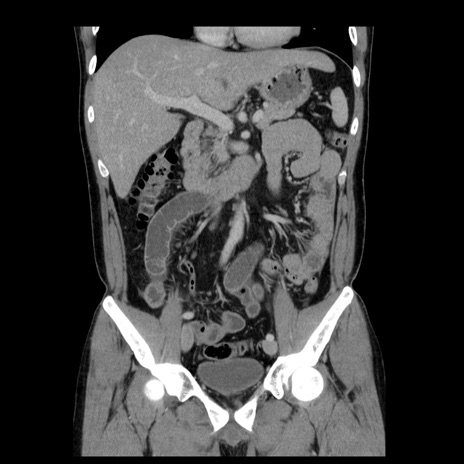

症例4(冠状断像)

【症例】30歳代男性

【主訴】腹痛、嘔吐

【現病歴】昨晩から突然の腹痛あり、その後嘔吐、軟便も出現。腹痛が改善しないため救急搬送となる。2日前にしめ鯖の食事歴あり。

【身体所見】意識清明、苦悶様、BP 135/90mmHg、BT 35.7℃、腹部:平坦、やや硬、心窩部〜臍部に自発痛、圧痛あり、筋性防御+、反跳痛-

【データ】WBC 8100、CRP 0.57